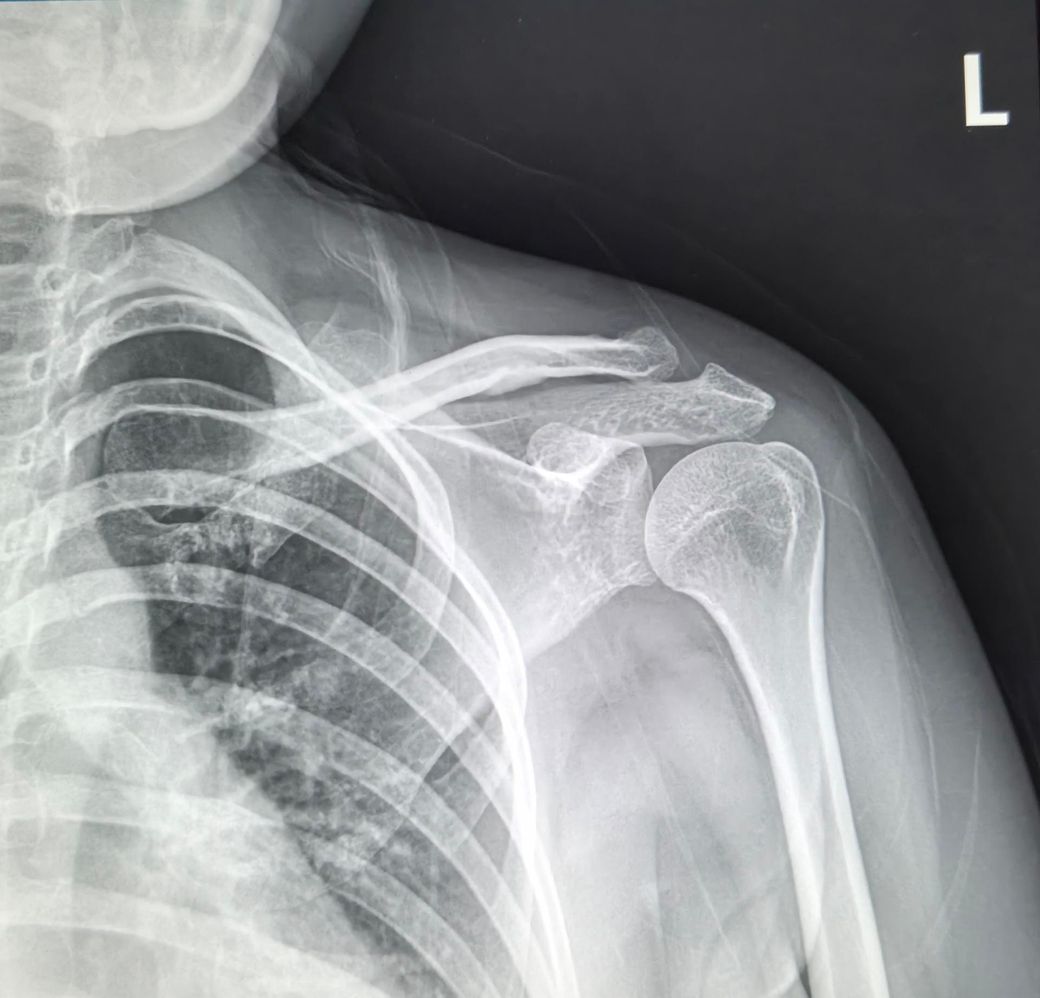

엑스레이사진은 왼쪽어께사진인데 1번 사진은

2025년10월14일사진이구요

2번사진은 2026년2월19일 사진입니다.

두 엑스레이 상에서도 다른점이 있나요?

견봉이랑 팔뼈 더 좁아지지는 않았나요?

사진만으로 확정 판독은 어렵지만, 말씀처럼 "과거 골절 후 유합되며 뼈 돌출(골극)" 소견이 보이고 견봉 하방이 비교적 뾰족해 보입니다.

두 X-ray를 비교하면 "견봉–상완골 간격이 아주 약간 더 답답해 보일 수는 있으나" 급격히 좁아진 소견은 뚜렷하진 않습니다.

엑스레이 두장의 사진만으론 판단을 하긴 어렵지만 확연히 공간이 좁아보이지만 이 부분이 엑스레이 촬영시 통증에 의한 보상작용으로 자세적인 문제로 인해 공간이 좁아보일수도 있기에 단정을 짓긴 어렵습니다.